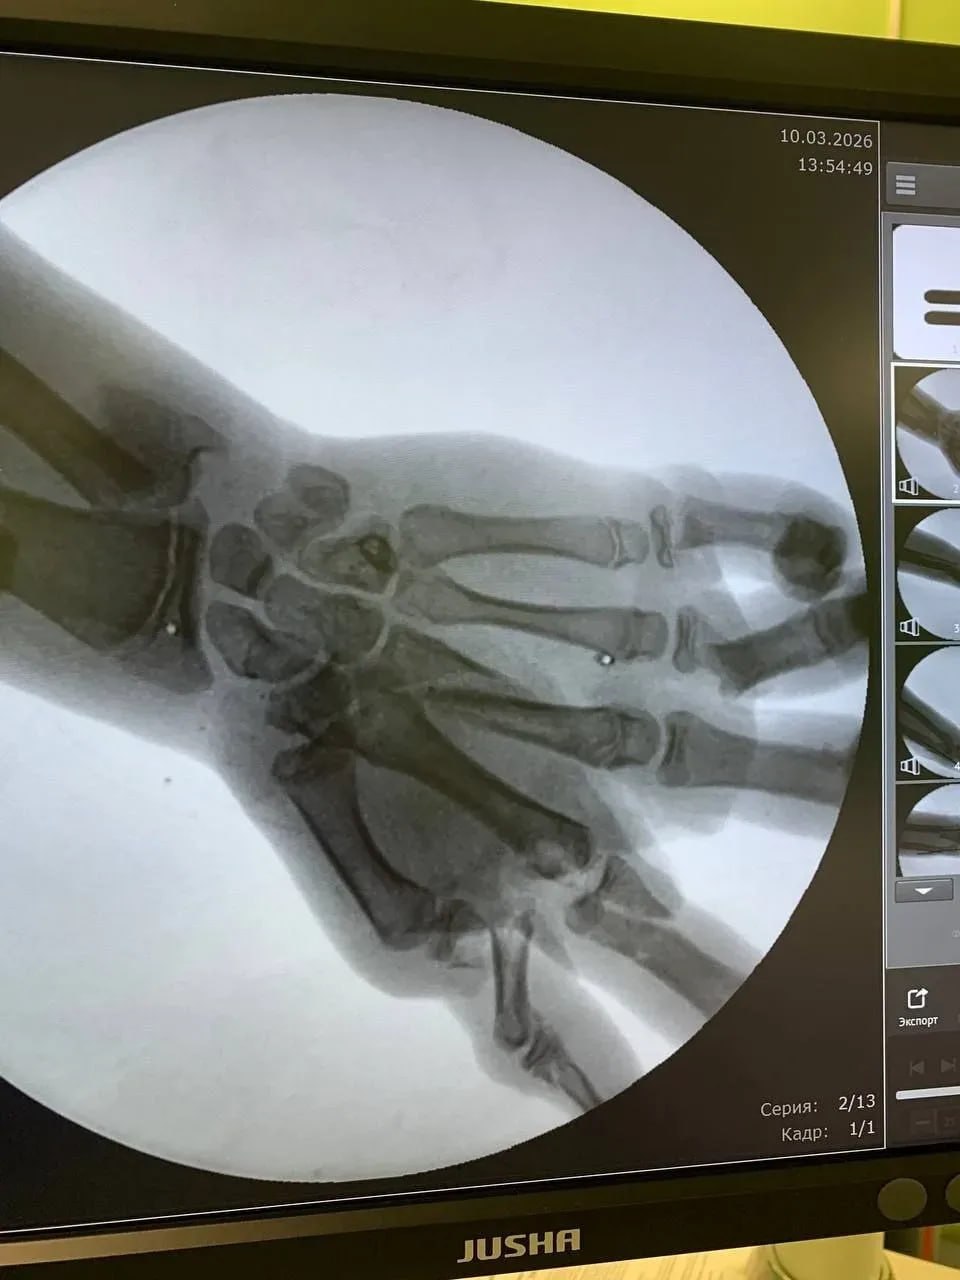

Мальчик получил множественные переломы кисти и сильное кровотечение.

Врачи смогли сохранить руку — кисть буквально собирали по частям, сообщили в областном минздраве.